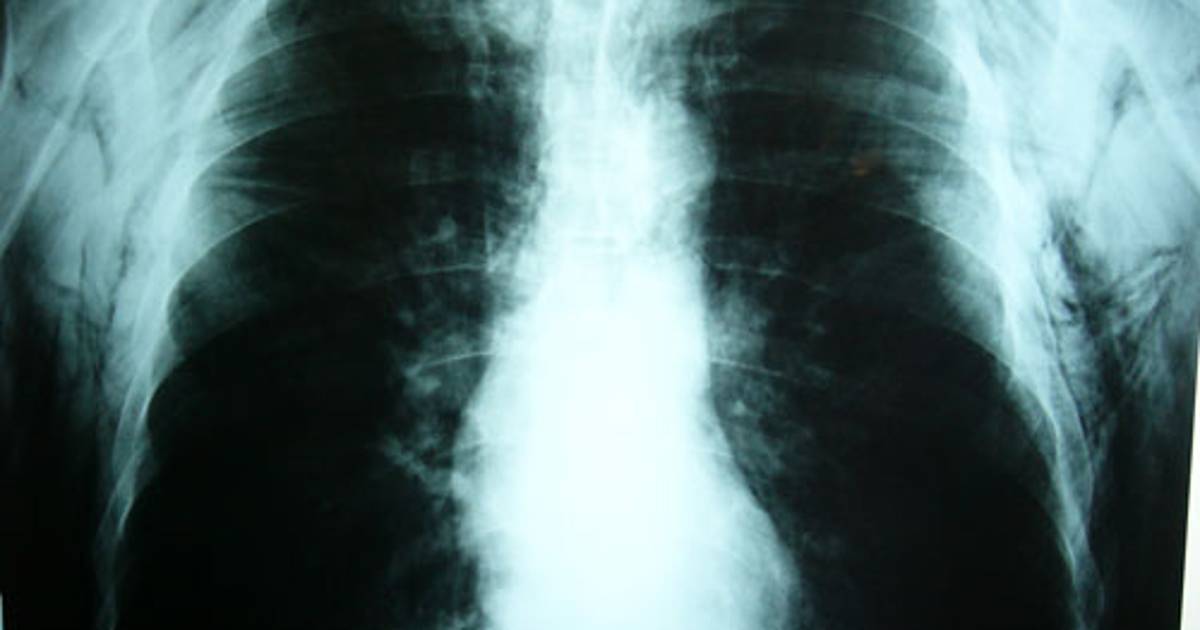

Los pulmones de pacientes que usaban aparatos para facilitar su respiración se regeneraron tras ser tratados con células madre extraídas de su médula ósea

Los pulmones de tres de los cuatro pacientes se regeneraron tras ser tratados con células madre extraídas de la médula ósea de los propios voluntarios. Esos tres pacientes ahora andan sin la necesidad de aparatos para facilitar su respiración.

Las células tronco fueron inyectadas en la corriente sanguínea de los voluntarios de forma que se alojaran en la región pulmonar. Estas células redujeron los espacios entre las paredes que forman el tejido donde el oxígeno es aprovechado por el cuerpo. El enfisema se caracteriza precisamente por las grandes cavidades que quedan en el tejido y que dificultan la respiración.